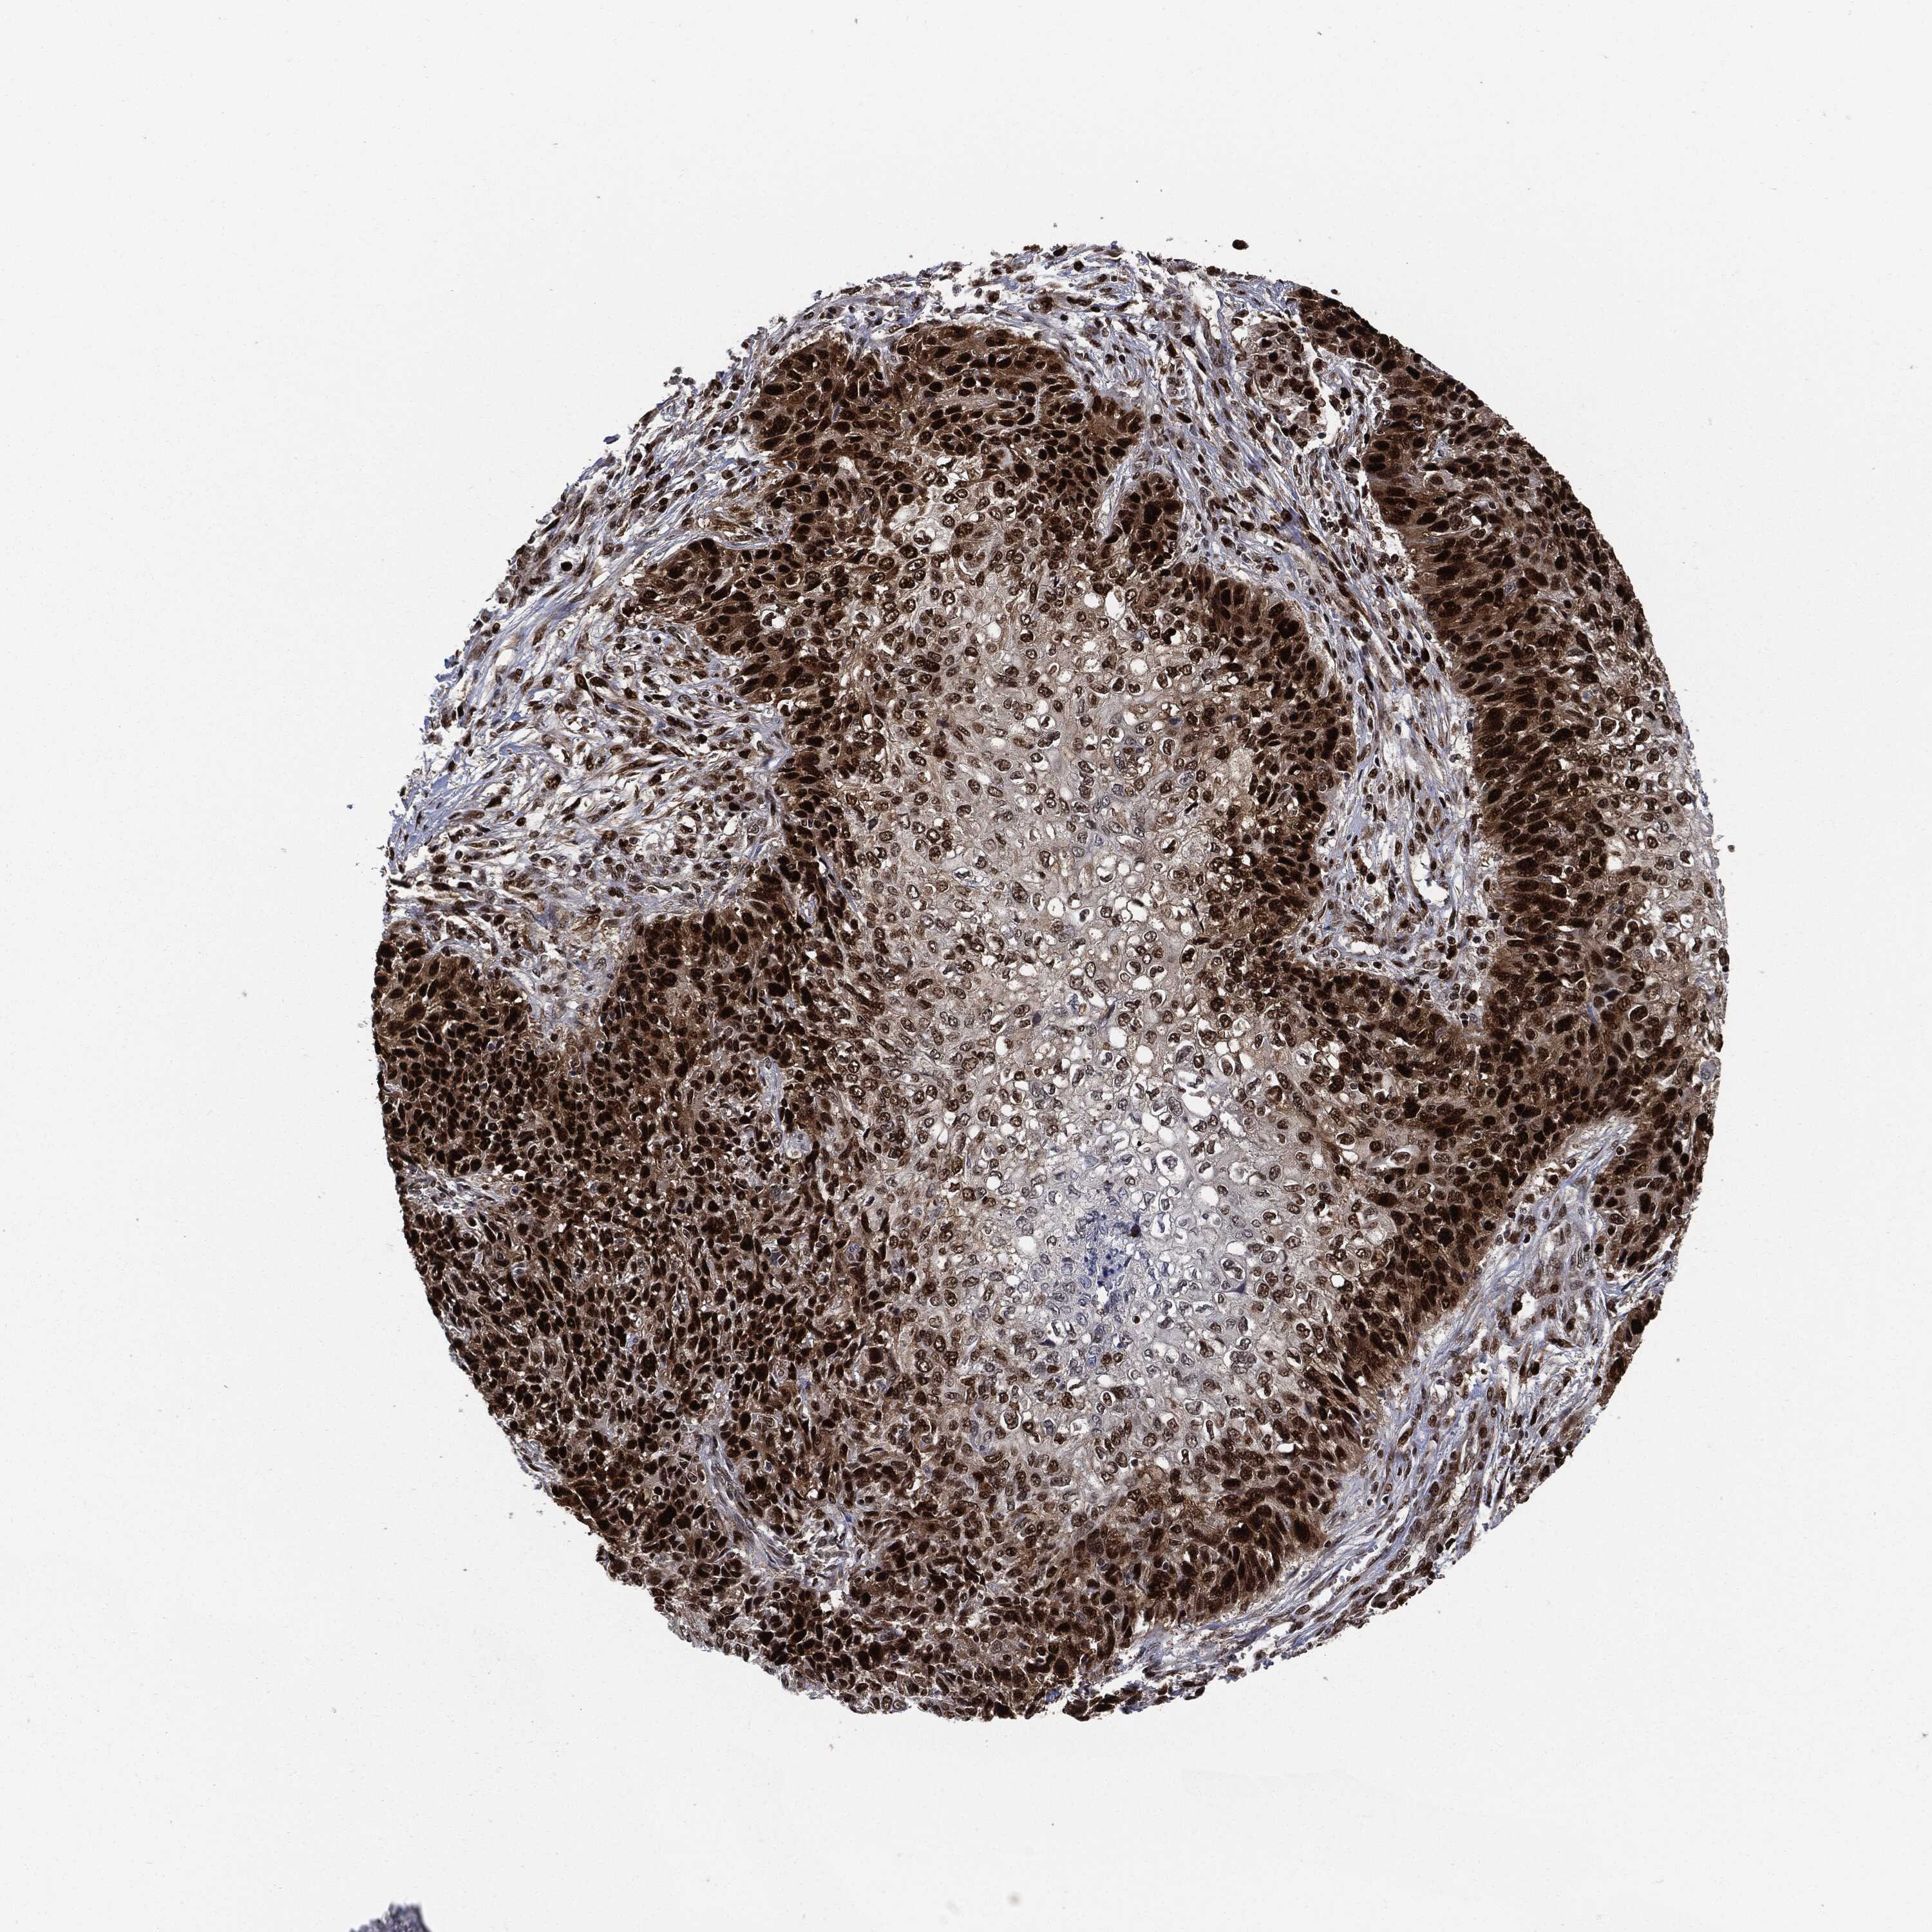

SKIN CANCER - Protein expressioni

A mouse-over function shows sample information and annotation data. Click on an image to view it in a full screen mode. Samples can be filtered based on level of antibody staining by selecting one or several of the following categories: high, medium, low and not detected. The assay and annotation is described here.

Each image is clickable and will lead to virtual microscopy that enables deeper exploration of all samples and also displays staining intensity scores, fraction scores and subcellular localization as well as patient and tissue information for each sample.

HPA030521

HPA030522

HPA030523

CAB000148

CAB080240

CAB080241

CAB080242

Staining

High

Medium

Low

Not detected

Intensity

Strong

Moderate

Weak

Negative

Quantity

>75%

75%-25%

<25%

None

Location

Nuclear

Cytoplasmic/membranous

Cytoplasmic/membranous,nuclear

Basal cell carcinoma

Squamous cell carcinoma, NOS

Squamous cell carcinoma, metastatic, NOS